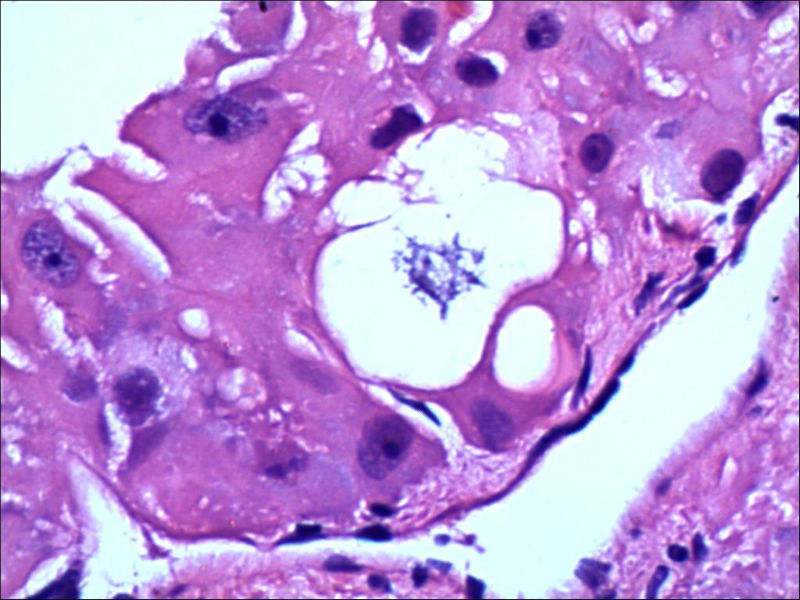

女,27岁,送检右侧卵巢肿物(另外还送检左侧卵巢肿物,大体及镜下显示为畸胎瘤),卵圆形,大小2×1×1cm,似有包膜。卵巢肿物图1

卵巢畸胎瘤中正常卵巢的黄体组织,铺砖样排列,胞浆宽大,较典型。

不好意思,可能是我没说清楚,患者对侧卵巢是畸胎瘤,不是同一侧的,我初步考虑门细胞瘤,图21,22,24,25,26中央的一些细胞是不是很像门细胞

谢谢大家的回答和解疑,忘记一个重要的病史,就是该女性为产妇。但是妊娠黄体瘤与类固醇细胞瘤怎么鉴别呢

那应该是妊娠黄体/黄体瘤,类固醇细胞瘤有嗜酸细胞和组织细胞样细胞两种,此例显然不是。